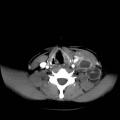

Dilatation des voies biliaires

DILATATION

PANCREATITE